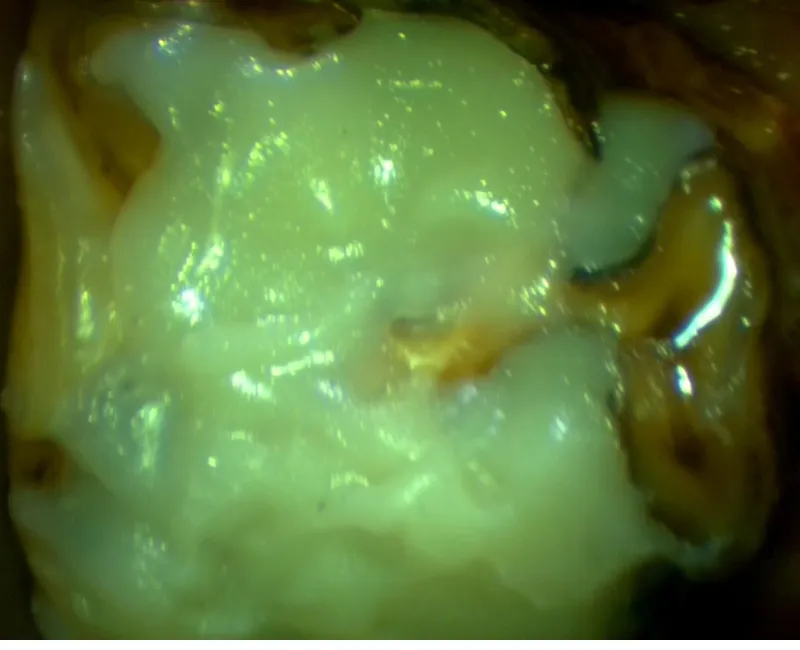

Jimmy was sedated and placed comfortably in the portable stocks for a full oral examination. The findings were significant. He had severe peripheral caries (decay on the sides of the teeth) and occlusal caries (decay affecting the grinding surface of the teeth) that had eaten deep into the protective layer over the pulp cavities (the inner chamber containing nerves and blood vessels).

The last three teeth in each arcade were the most severely affected, with much of the clinical crown (the visible part of the tooth above the gum line) eaten away to the level of the gum. Only small islands of enamel remained around the edges, forming perfect “caves” that trapped feed. This trapped material provided a constant food source for bacteria, accelerating decay and infection.

The peripheral caries had also eaten into the sides of the lower teeth, creating gaps where feed became wedged, causing secondary periodontal disease (infection between the teeth and under the gums). Several pockets of infection up to 10mm deep below the gumline were found.

A fluoride varnish was applied to the areas of decay to help remineralise the dental materials and slow further damage until a follow-up appointment could be scheduled. Given the extent of decay, occlusal restorations (fillings) were recommended to prevent the infection from spreading into the pulp cavities.

Eight teeth required restorations. The severely decayed material was carefully removed using precision dental drills until only the stronger, healthy dental material remained. The tooth surfaces were then shaped to create small ledges for retention (macromechanical retention), acid-etched, rinsed, and bonded. Finally, bulk-fill resin composite, a durable human dental material, was applied to restore the tooth’s shape and function.